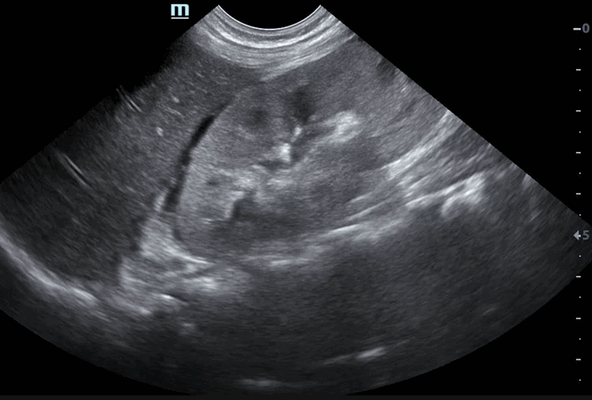

Метастазы. Эти злокачественные новообразования обычно выявляются в области коры. Метастазы могут быть обнаружены как в одной, так и в обеих почках. Такие опухоли имеют вид гипоэхогенных объемных образований различного размера и формы.

Почечные метастазы обычно двусторонние мультифокальные поражения небольшего размера, с инфильтративным характером роста. Образования умеренно усиливаются при контрастировании, намногим больше, чем нормальная почечная паренхима. Метастазы также могут быть «гиперваскулярными» при меланоме, а иногда при раке молочной железы.

На изображении пациента визуализируется несколько почечных метастазов.

Обратите внимание на опухолевый тромб в левой почечной вене.

Представлен пациент с раком легких.

Метастазирование в левую почку и множественное метастазирование в лимфоузлы (стрелки).

Если бы не было анамнеза то, было бы трудно отличить от почечно-клеточного рака с метастазами в лимфоузлы.